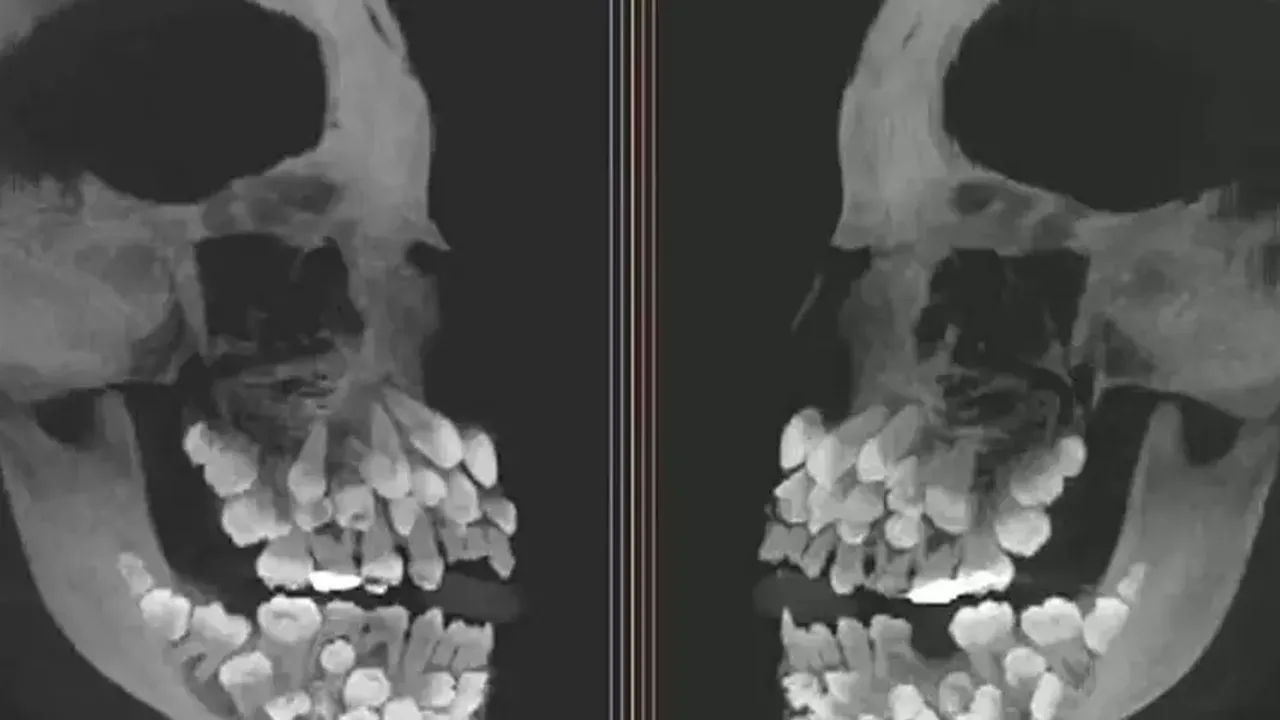

Doktorlar, çene röntgenine baktıklarında gözlerine inanamadı. Genç kızın ağzında tam 81 diş vardı yani normalin neredeyse üç katıydı. Üstelik bu fazla dişlerin bir kısmı damakta görünürken, büyük kısmı etin içinde, henüz yüzeye çıkmamış şekilde saklanıyordu.

Peki bu kadar fazla dişe neden sahipti? Üstelik hiçbir sendrom ya da kalıtsal rahatsızlık belirtisi yoktu. Genetik testler, 9. kromozomda yapısal bir bozukluğu işaret etse de, uzmanlar hala bu durumun nedenini kesin olarak açıklayamıyor. Dişlerin boyutları ve konumları da son derece ilginçti; bazıları gelişimini tamamlamıştı, bazılarıysa minyatür şekilde, adeta çene içinde saklanmış bir "diş müzesi" gibiydi.